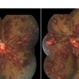

- Roth spots, anaemic retinopathy

- 22-year-old male with systemic dengue fever and anaemia presenting with roth spots in both eyes (OD>OS). Horizontal raster OCT scans showing intraretinal foveal hameorrhage in right eye.